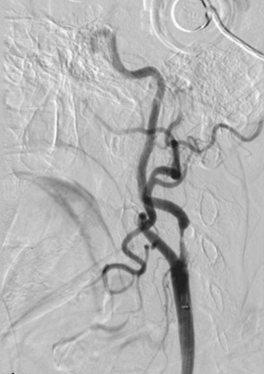

【111-1 醫學(五) 第29題】80歲男性抽菸且合併高血壓、糖尿病病史,接受頸動脈血管攝影檢查之結果如附圖。則下列敘述何者錯誤?

這題的關鍵在於正確判讀頸動脈血管攝影(carotid angiogram),辨識出狹窄(stenosis)的位置。影像清楚顯示狹窄發生在內頸動脈(internal carotid artery),而非外頸動脈(external carotid artery)。